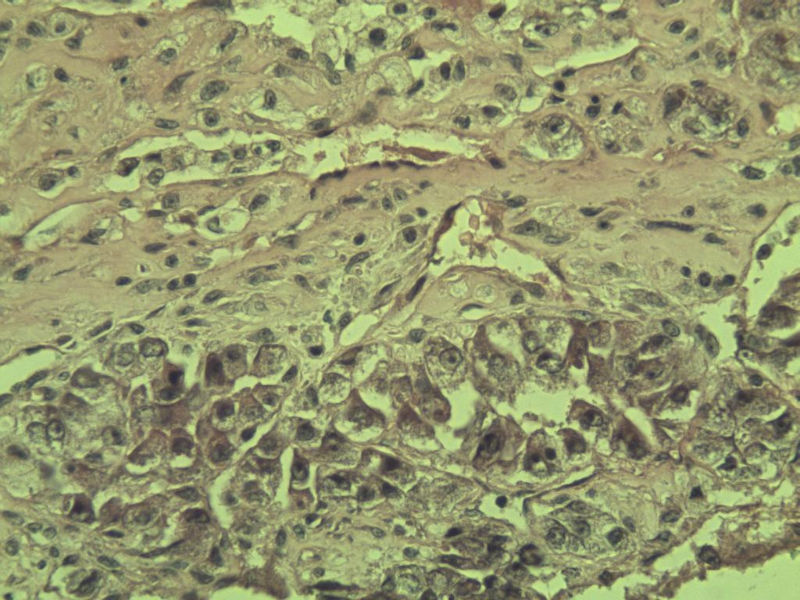

女 70岁 右颈部 头皮 多发皮下结节 取颈部部分结节送检 灰白小组织 1 块,直径 0.4 cm。 请问这个是什么?